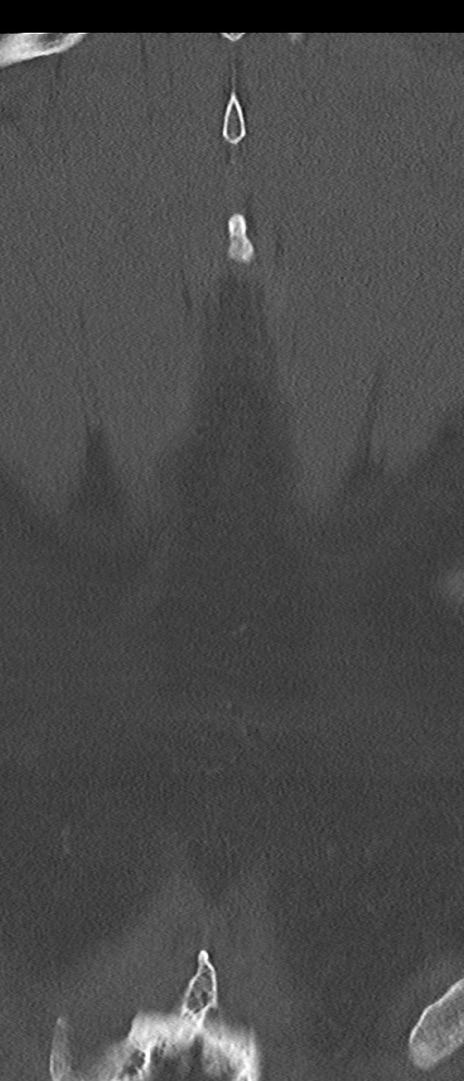

腰椎CT

矢状断像